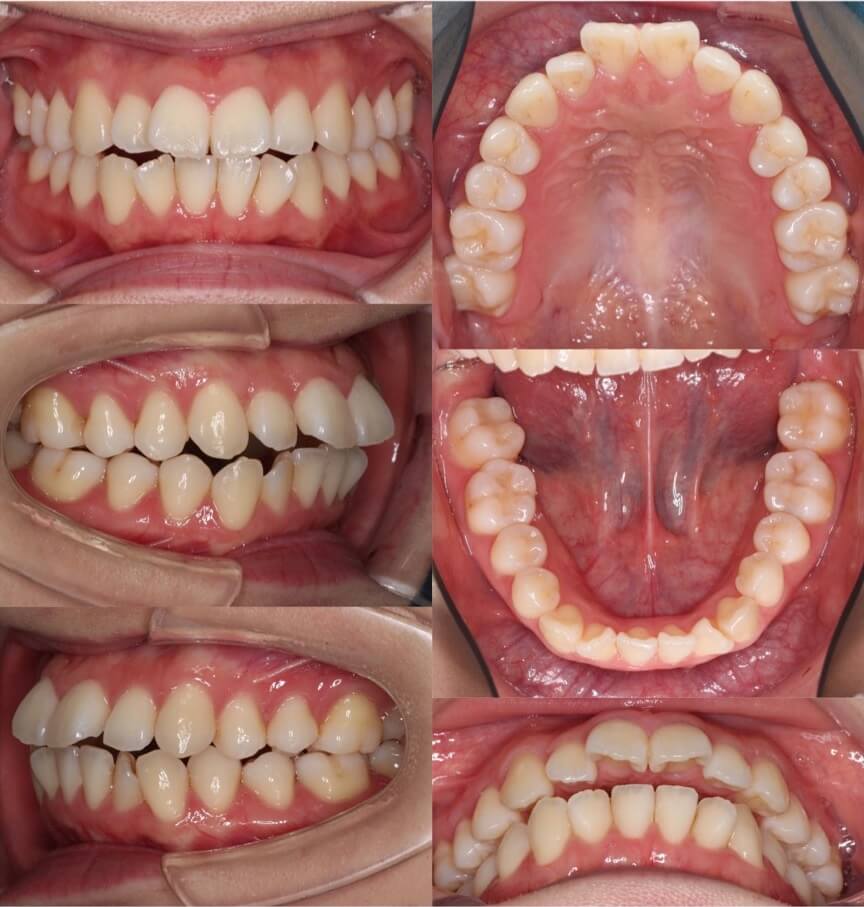

「顔のサイズが小さくなる」

大学生女性・ハーフリンガル装置・前歯傾斜型装置・下あご後退型

歯並びの見た目はあまり悪くはないのですが、口元のの突出の改善を希望されていました患者さんです。上下顎抜歯を併用して矯正治療を行いました。ゆっくりとお顔が変化するのを楽しんで治療を受けてくれていました

<症例概要>

主訴:出っ歯を治したい

年齢・性別:大学生女性

住まい:千葉県八千代市

症状:下顎後退・上下顎前歯唇側傾斜

治療方針:抜歯空隙の閉鎖(最大固定)

治療装置:ハーフリンガル矯正装置(上のみ裏側装置)

固定:歯科矯正用アンカースクリュー(口蓋側壁x2)

抜歯:上下第一小臼歯

治療期間:2年1か月

リテーナー:上プレートタイプ+クリアタイプ・下フィックスタイプ

治療費用:1,495,000(税込)

代表的副作用:痛み・治療後の後戻り・歯根吸収・歯髄壊死・歯肉退縮

▶︎その他の副作用